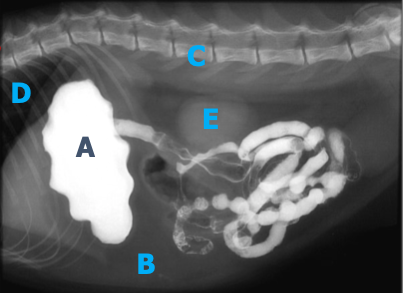

Nommez les opacités de chaque lettre.

a) métal

b) gras

c) minérale

d) air

e) tissu mou

Quel est votre conclusion radiographique? Énumérez quelques diagnostics différentiels.

=> masse splénique

Ddx : néoplasme, granulome, kyste, hématome, nodule hyperplasique